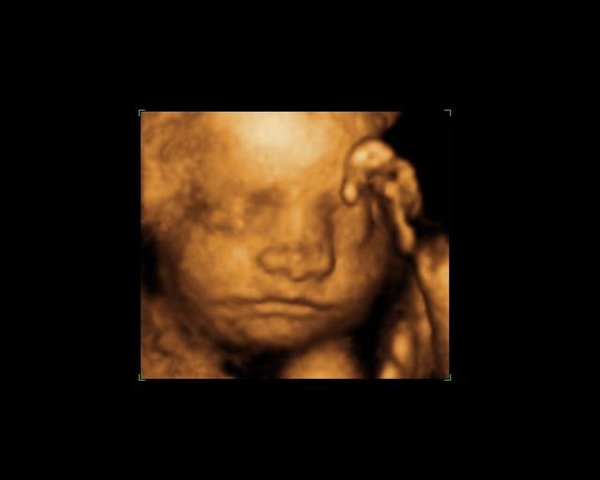

Dernæst havde vi bestilt tid til en privat 3d/4dscanning på scanningsklinikken i København, men den første gang lå hun med hænderne foran ansigtet, så vi blev tilbudt en ekstra gratis.. Det samme skete så anden gang igen og så var de så søde at vi fik en tredje gang, og så kunne vi endelig se hendes smukke ansigt

Knus Rikke og lille Liva..